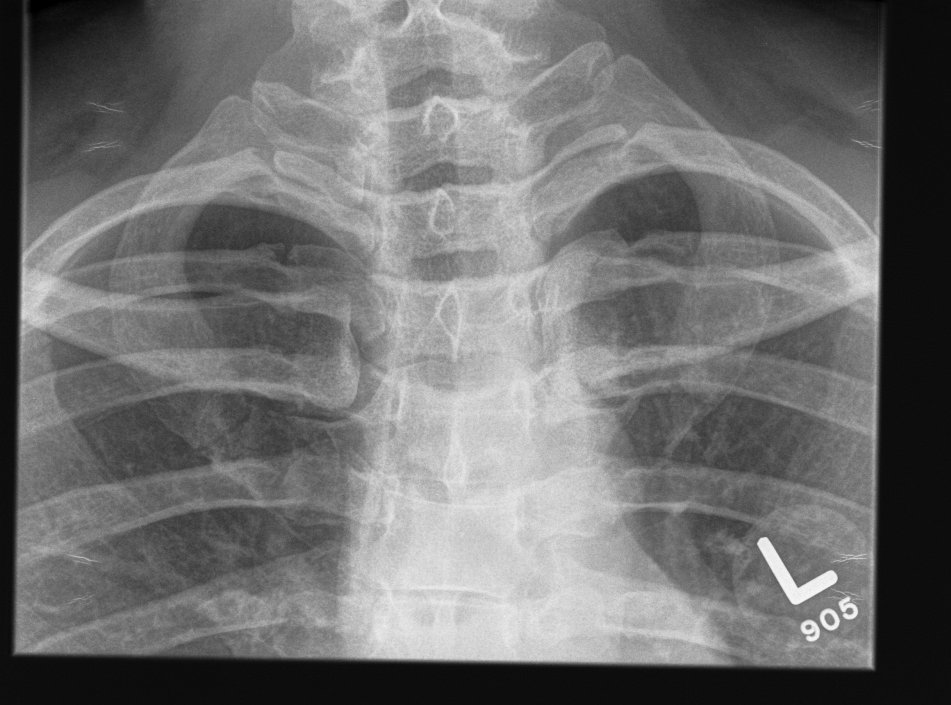

Xray

Can be missed on a xray